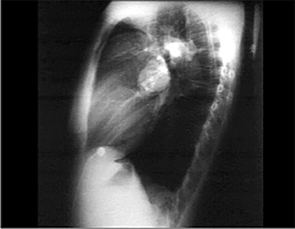

PA and Lateral

Click on the Xrays to enlarge them.

Choose the best interpretation of the chest X rays:

RV enlargement + ↓ pulmonary trunk + ↓ pulmonary vascularity

RV enlargement + ↑ central pulmonary

arteries + ↓ peripheral markings

RV enlargement + dilated pulmonary

trunk + ↑ pulmonary vascularity

RV enlargement +

left atrial enlargement

Bilateral pulmonary fibrosis +

mild cardiomegaly